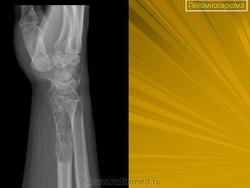

Внутрикостная лейомиома

https://www.ncbi.nlm.nih.gov/pmc/articles/PMC5040582/

Дооперационные рентгенограммы.